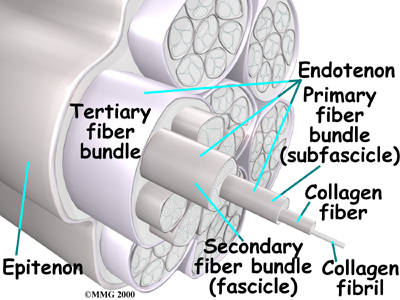

Ligaments are the soft tissues that attach bones to bones. Ligaments are very similar to

tendons. The difference is that tendons attach muscles to bones. Both of these structures are made up of small fibers of a material called . The collagen fibers are bundled together to form a rope-like structure. Ligaments and tendons come in many different sizes and like rope, are made up of many smaller fibers. Thickness of the ligament or tendon determines its strength.